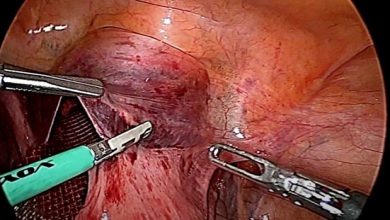

vNotes Hysterectomy – Cihan Kaya

Septum Rezeksiyonu

Tubal Polip

Vajinal Asiste Laparoskopik Seklaj Pektohisteropeksi – Dr. Çağlar Çetin

LİGHTED LS HİSTEREKTOMİ – Op. Dr. Seda ŞAHİN AKER